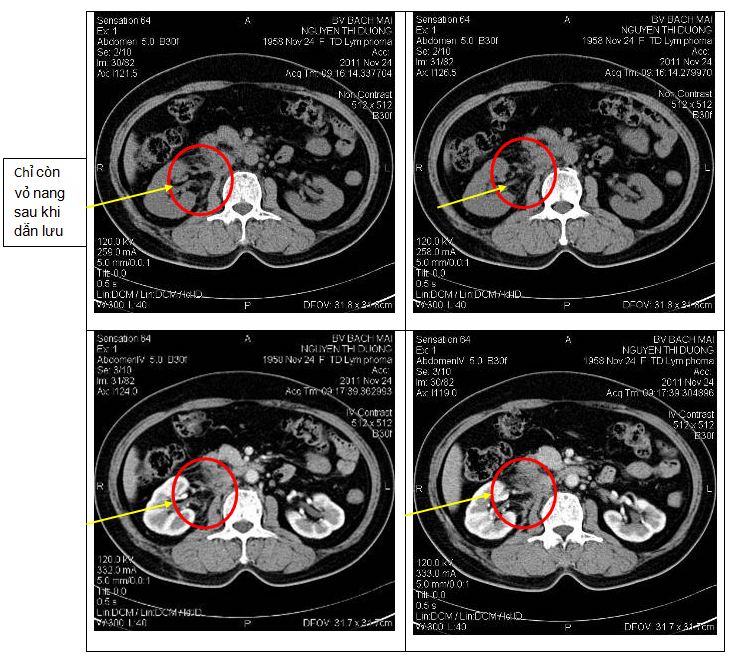

Bệnh nhân được chụp lại phim cắt lớp vi tính 64 dãy ổ bụng để đánh giá tình trạng bệnh cho thấy tổn thương u đã tan hết, không thấy hình ảnh khí và dịch trong nang, còn tồn tại vỏ nang. Không thấy rõ hình ảnh sỏi thận 2 bên, niệu quản 2 bên không giãn. Nang thận trái đường kính 1cm

Sau 24 giờ tiến hành chụp CT ổ bụng đánh giá thấy hình ảnh dẫn lưu đặt đúng vị trí khối tổn thương u, có hình ảnh khí trong khối tổn thương.